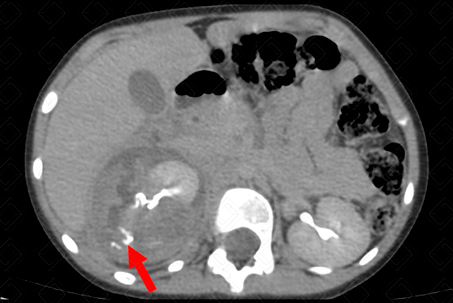

Texto alternativo para a imagem Figura 2. Créditos: Dra. Elazir Mota - Rio de Janeiro/RJ

Descrição da figura 2: Tomografia computadorizada do abdome do mesmo paciente, fase tardia (fase excretória) onde se observa presença de extravasamento do meio de contraste (seta vermelha), indicando rompimento do fórnix renal (urinoma). O conjunto de achados categorizam paciente no trauma renal grau II.

• Grau II: Lacerações maiores através do córtex e estendendo para medula renal ou sistema coletor, com ou sem urinoma ou infarto segmentar (f iguras 1 e 2);